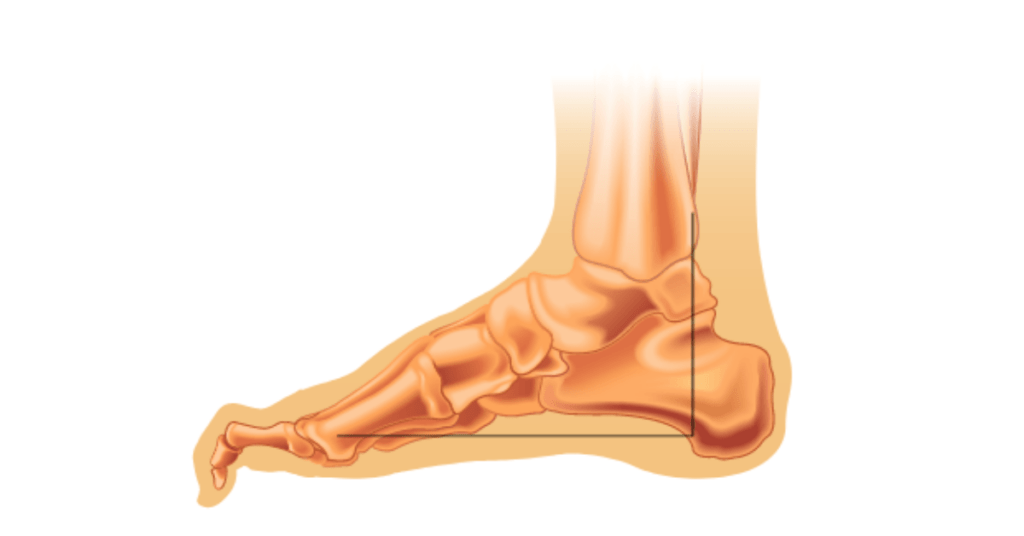

Wat zijn hamertenen? Hamertenen, is een aandoening waarbij één of meerdere tenen in een kromme positie blijven staan. De teenkootjes buigen op onnatuurlijke wijze naar beneden waardoor de teen eruitziet als een hamer. Dit kan leiden tot ongemak, pijn en moeilijkheden bij het vinden van geschikt schoeisel. De vergroeiing kan voorkomen in iedere teen, maar […]